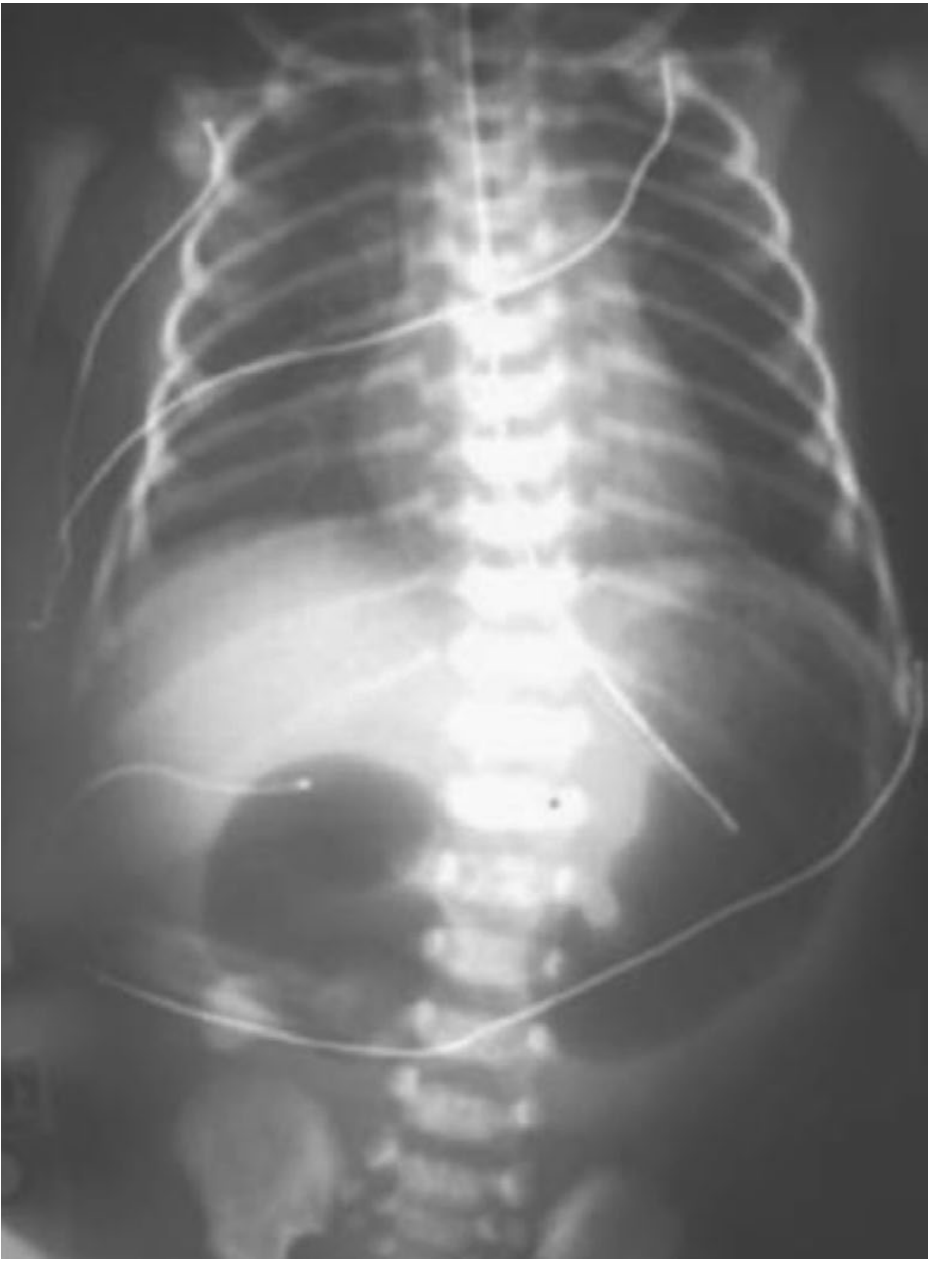

The pathognomonic radiographic finding is the "double-bubble" sign — two gas-filled, fluid-filled chambers representing the distended stomach and the proximal duodenum, with no gas beyond the obstruction.

Plain abdominal radiograph showing the double-bubble sign of duodenal atresia — distended stomach (left bubble) and proximal duodenum (right bubble) with absent distal gas

Plain abdominal radiograph: classic double-bubble sign in duodenal atresia. — Sabiston Textbook of Surgery

• If distal gas is present, an upper GI contrast study should be performed to exclude malrotation with midgut volvulus (a surgical emergency)

• Prenatal ultrasound shows fluid-filled double-bubble in the fetal abdomen